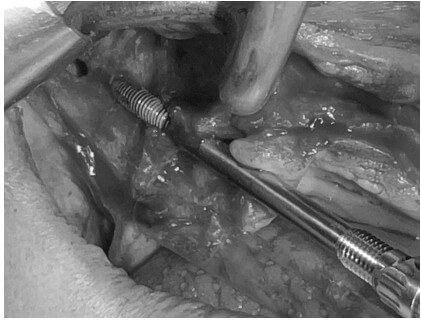

Colocamos los implantes cigomáticos según las guías quirúrgicas que hemos diseñado en planificación 3D.

Podemos hacer carga inmediata. Todo se realiza bajo sedación intravenosa monitorizada

Planificación 3D y confección de férulas quirúrgicas para abordaje guiado.

Se colocan 4 implantes Zygoma según planificación 3D guiada bajo sedación IV, Carga inmediata a las 24 horas.